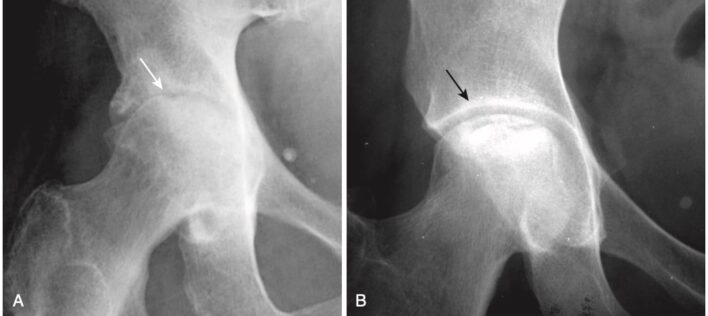

Hình 2. Hình ảnh nào là viêm khớp? A, Có hẹp khe của khớp háng, và cả chỏm xương đùi và ổ cối đều bất thường (mũi tên trắng). Đây là bệnh thoái hóa khớp háng. B, Có bất thường chỏm xương đùi (đặc xương), nhưng khe khớp còn nguyên vẹn, cũng như ổ cối (mũi tên đen). Đây là hoại tử vô mạch của chỏm xương đùi.